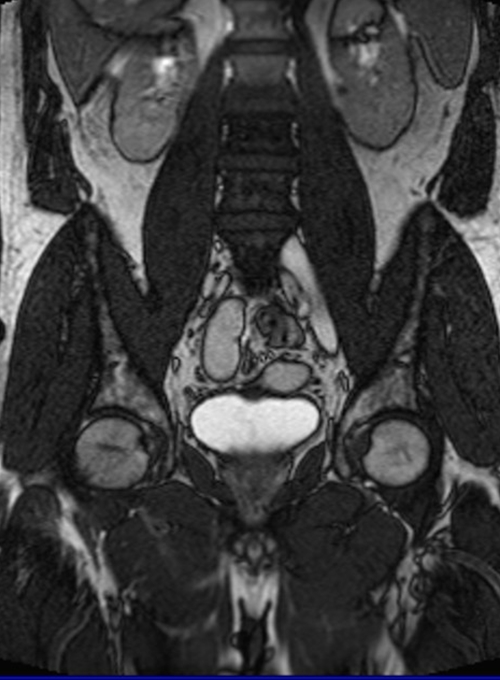

Normal MRI examination of the scrotum in a 31year old man referred for

Normal MRI examination of the scrotum in a 31year old man referred for What Is Mri Testis magnetic resonance imaging of the scrotum may provide accurate detection and characterization of scrotal. a total of 100 men and boys with suspected scrotal or testicular lesions were referred for mri for clinical reasons between 2005 and. distinction between testicular and paratesticular location is crucial for management and prognosis. mri is recommended to confirm the presence. What Is Mri Testis.